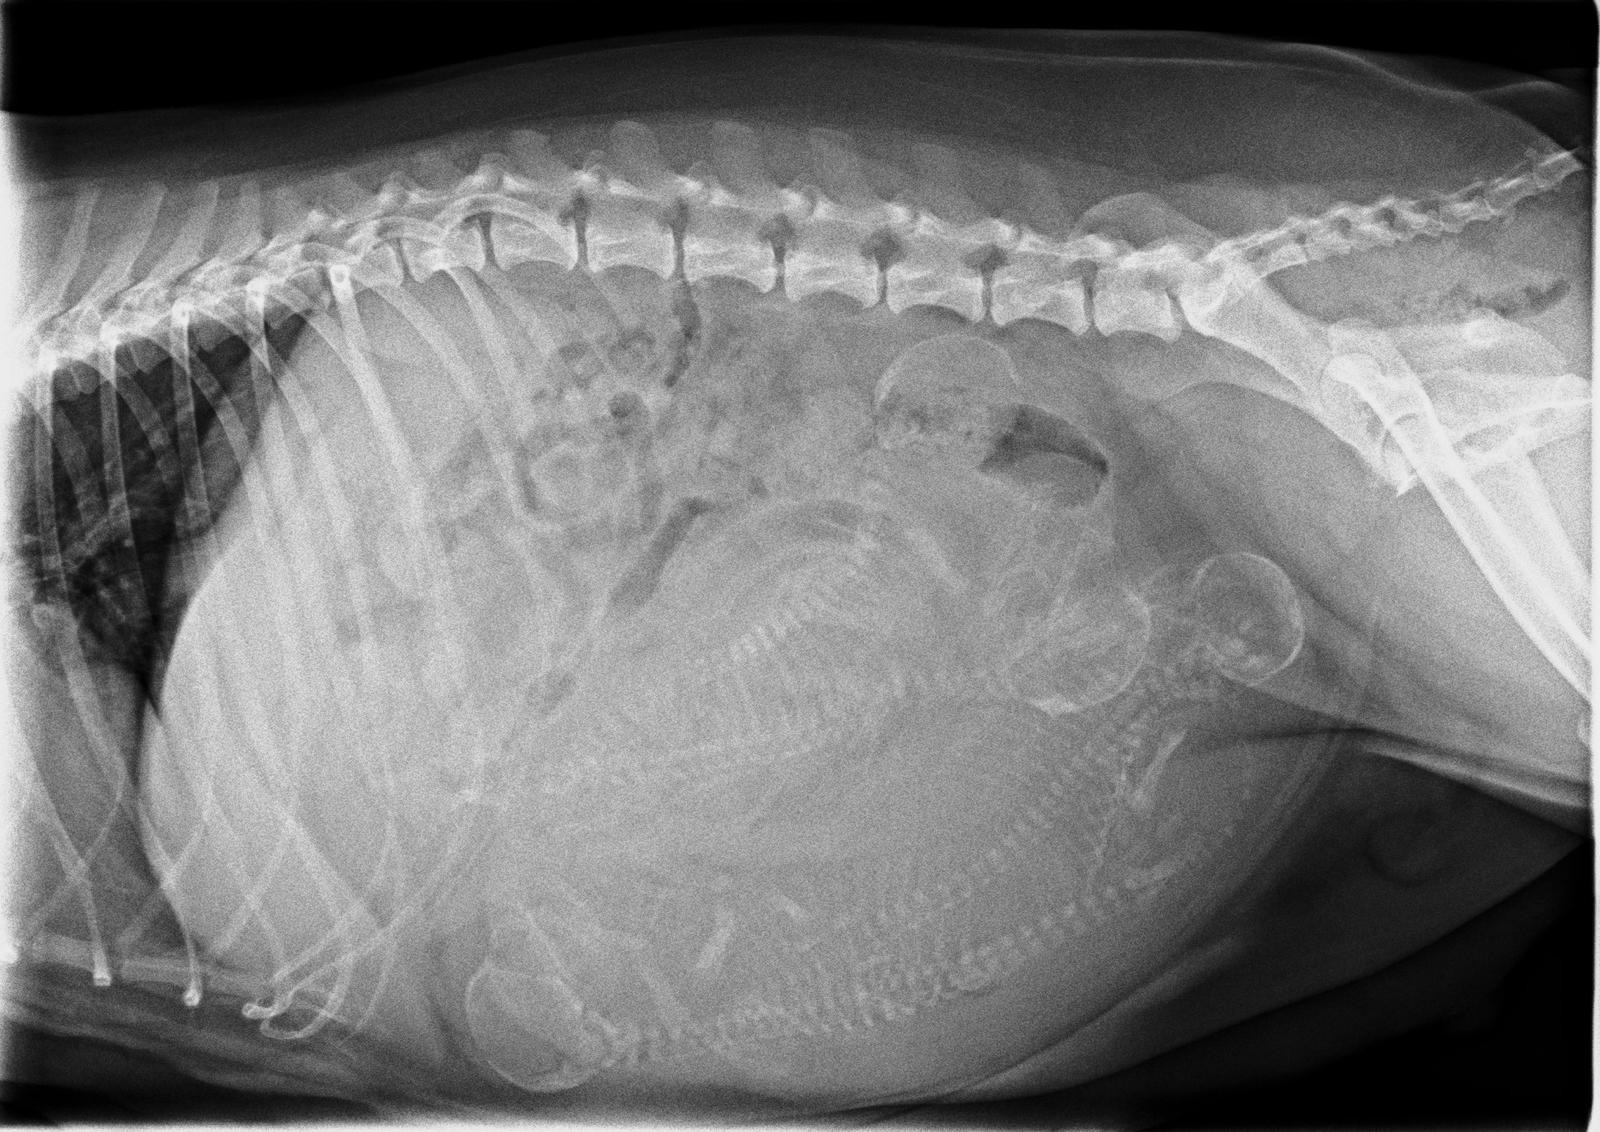

Rund 1 Woche vor dem berechneten Wurftermin war unsere Maite vom Nikolausberg bei unserer Tierärztin Dr. Marianne Fischer zum Röntgen. Wir wollten ja wissen, mit wie vielen "Fellnasen" wir rechnen können, auch um bei der Geburt etwas mehr Sicherheit zu haben, dass alles problemlos abläuft. Deutlich zu sehen sind 4 kleine Vierbeiner. Maite's Gewicht und Bauchumfang nehmen fortlaufend zu und sie ist etwas ruhiger geworden, kann, wie immer, nicht genügend zu fressen bekommen.

Inzwischen messen wir morgens und abends auch ihre Temperatur. Eines der Anzeichen, dass die Geburt kurz bevorsteht (ca. 12-36 Std. vorher) ist meistens, wenn die Temperatur um 1 Grad Celsius fällt.Wir sind also vorbereitet und so gespannt auf den Wurftag unseres A-Wurfs und freuen uns auf die Kleinen. Mal sehen, wie sich dann auch Papa Duke Ellington verhält...